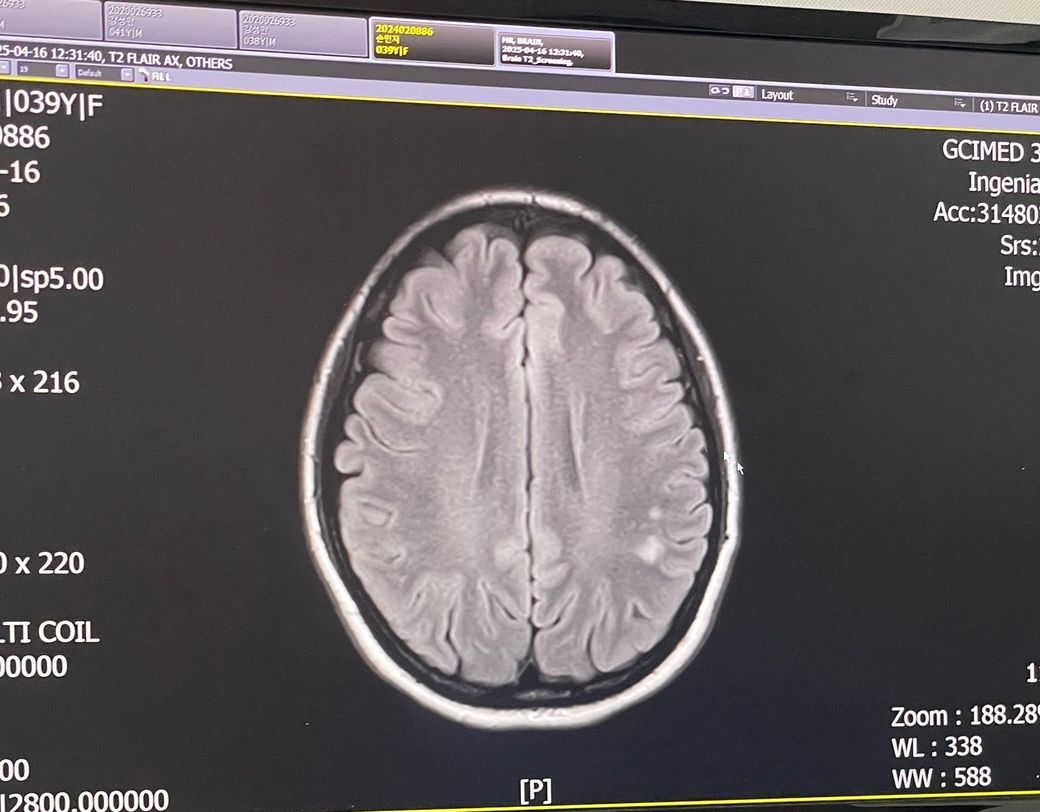

뇌 mri t2 스크리닝- 좌측 두정엽 뇌질 고신호 강도로 소혈관질환 의심 소견

• 1번 째 사진

말씀하신 내용만 토대로해서 대답해 드리자면 뇌 MRI에서 "좌측 두정엽 뇌질 고신호 강도"로 소혈관질환 의심 소견이 나왔다는 것은 작은 혈관에 문제가 있을 가능성이 있다는 것을 의미합니다. 일반적으로 이러한 소견은 소혈관성 질환이나 미세혈관 질환에 의해 발생할 수 있으며, 뇌졸중이나 기타 뇌혈관 질환의 전조 증상일 수 있습니다. 하지만, 소견만으로는 급성 질환 여부를 판단하기 어려우므로, 추가적인 검사와 세밀한 평가가 필요해요